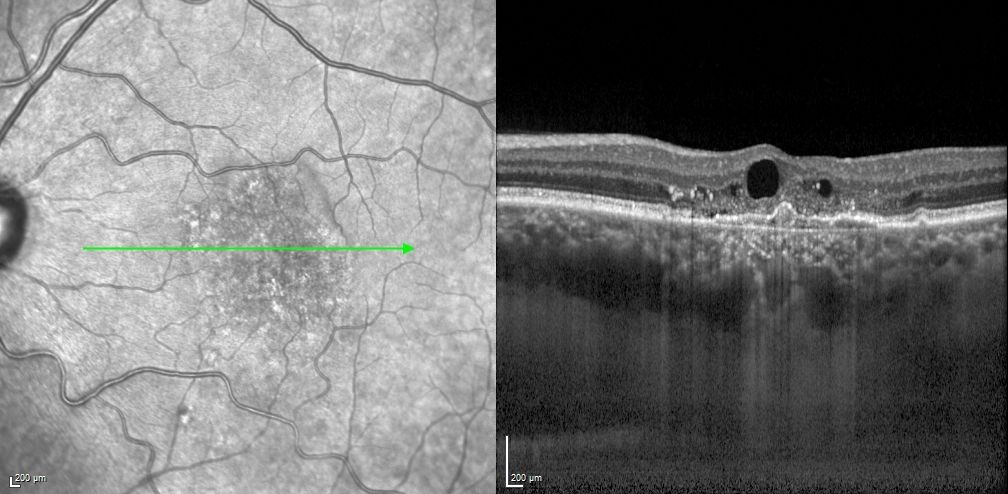

✚ OCT maculaire

Analyse structurelle révélant :

• Un œdème intra-rétinien

• Un décollement de l’épithélium pigmentaire de type FIPED (Flat Irregular Pigment Epithelium Detachment)

• La présence d’un micro-polype

• Une choroïde épaissie